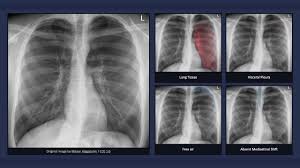

Pneumothorax X Ray / Pt Trick For Pneumothorax Types Symptoms Risk Factors Causes And Treatment Of Collapsed Lung Ezmed : The air then fills the space outside of the lung, between the lung and chest wall.. Air can enter the pleural space by two mechanisms, either. Jul 02, 2021 · a collapsed lung occurs when air escapes from the lung. Search only for pneumothorax x ray The degree of collapse determines the clinical presentation of pneumothorax. The air accumulation can apply pressure on the lung and make it collapse.

Air can enter the pleural space by two mechanisms, either. Search only for pneumothorax x ray It occurs when air accumulates between the parietal and visceral pleurae inside the chest. Aug 11, 2021 · fenton 2013 growth calculator for preterm infants. The air accumulation can apply pressure on the lung and make it collapse.